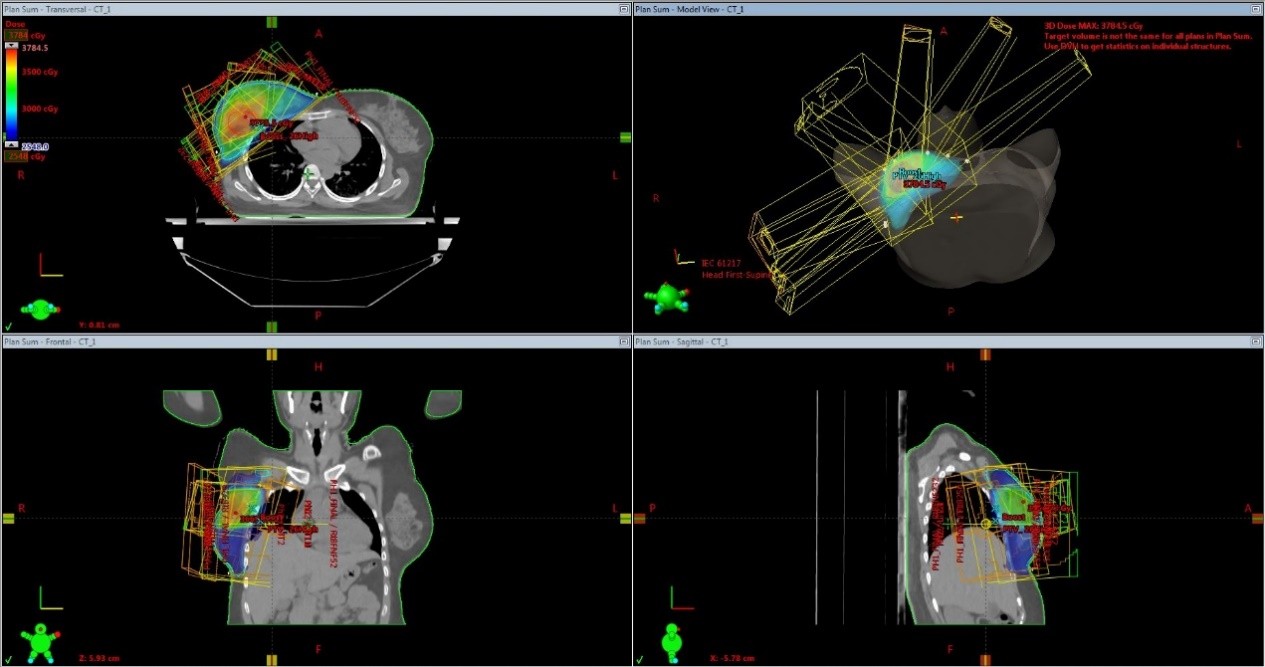

Treatment execution and daily treatment verification

The patients were treated on Varian truebeam 120 MLC machine.Barrier film spray was used on the breast or chestwall skin prior to each treatment session as per the department protocol aiming at reduction of acute radiation dermatitis. Daily onboard  image verification was ensured with KV images and cone beam CT scan (Picture 5).Portal images were also taken to confirm the central lung distance from  the posterior edge of the tangential field.Patients were educated well on skin care during the course of radiotherapy and during the follow up period.On the final day of radiotherapy,patients were clinically assessed along with photographic documentation .All patients were advised to apply betamethasone ointment all over the irradiated area  two times daily for two weeks.

Picture 5-Daily onboard imaging